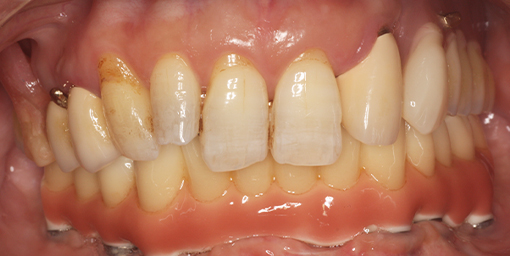

取り外しの入れ歯でなくしっかり食事を楽しみたい【オールオン5・インプラント・虫歯治療(保険診療)】